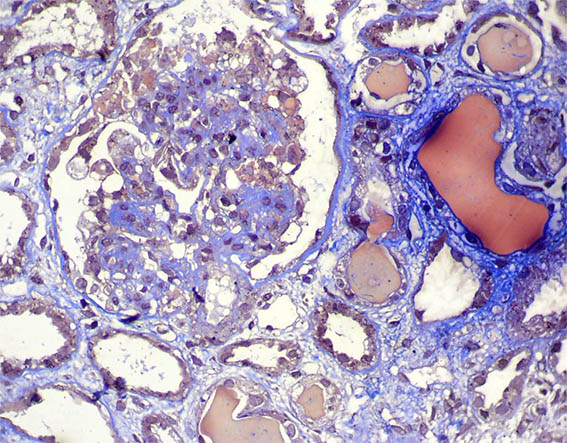

Figure 5. Masson´s trichrome, X400.